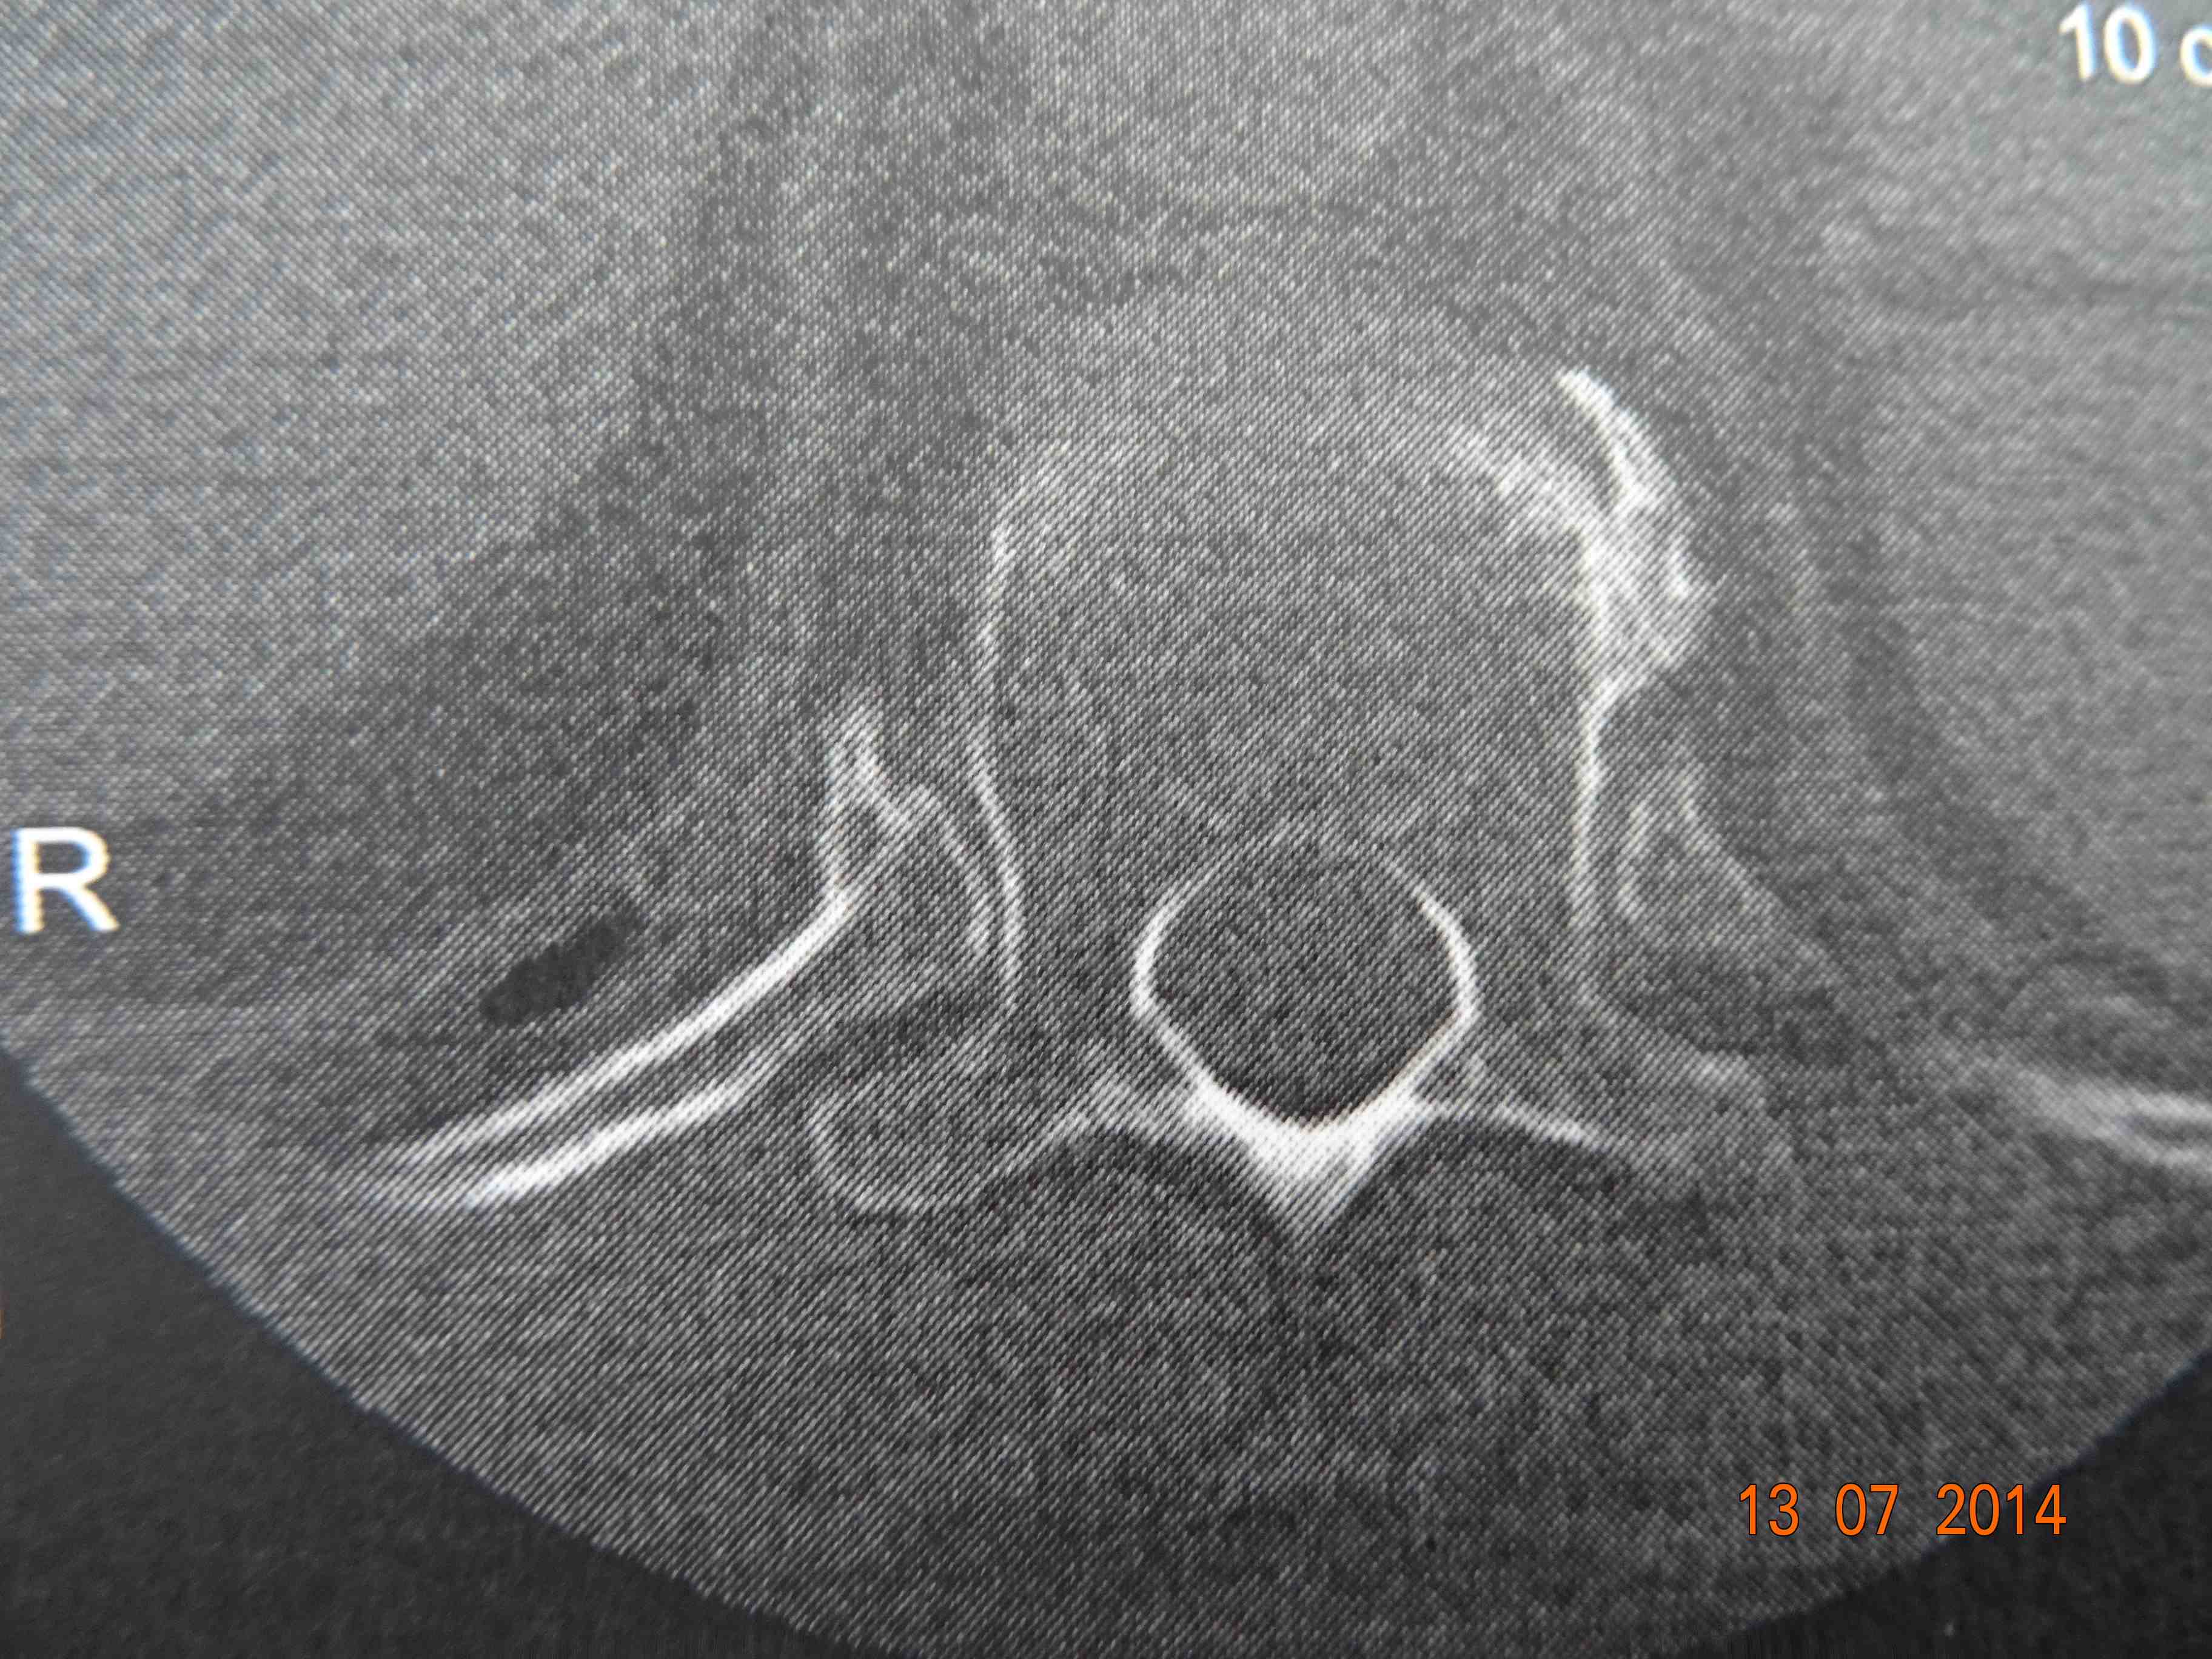

A few weeks ago I had a scan on my back. I'd left the CD with thousands of images of my spine/vertebrae with Camille (my friend and doctor). He gave them back to me at the meet (he is a member of the course committee, owns a horse and is the doctor in charge to attend to fallen jockeys, usually dislocated shoulders). So here is a picture of a good vertebrae and my broken one.

This is how a "normal" vertebrae should look.

The paper print doesn't show all the pictures on the CD so I've drawn two that illustrate my vertebrae.

This is my fractured vertebrae. These images are photos of the paper printout that came with the CD. On the CD is an image of the other side (not sure if this is from top or bottom). From the other side it looks like 2 ovals separated by a clear gap.